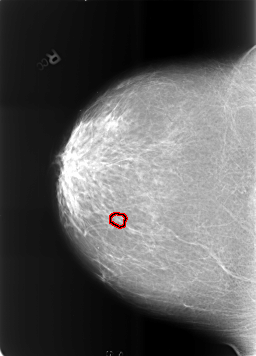

FILE: B_3465_1.RIGHT_CC.OVERLAY

TOTAL_ABNORMALITIES 1

ABNORMALITY 1

LESION_TYPE CALCIFICATION TYPE PLEOMORPHIC DISTRIBUTION CLUSTERED

ASSESSMENT 4

SUBTLETY 2

PATHOLOGY BENIGN

TOTAL_OUTLINES 1

BOUNDARY